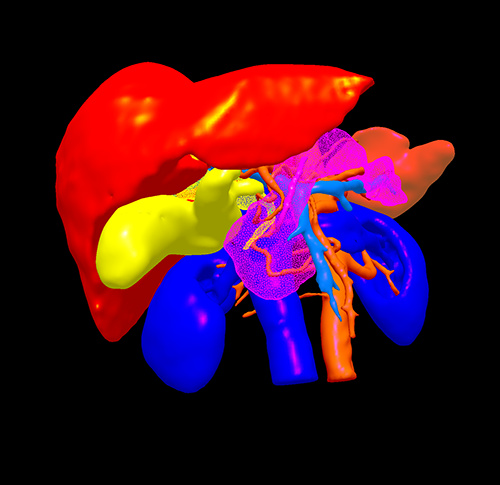

胆总管下端癌--胰十二指肠切除